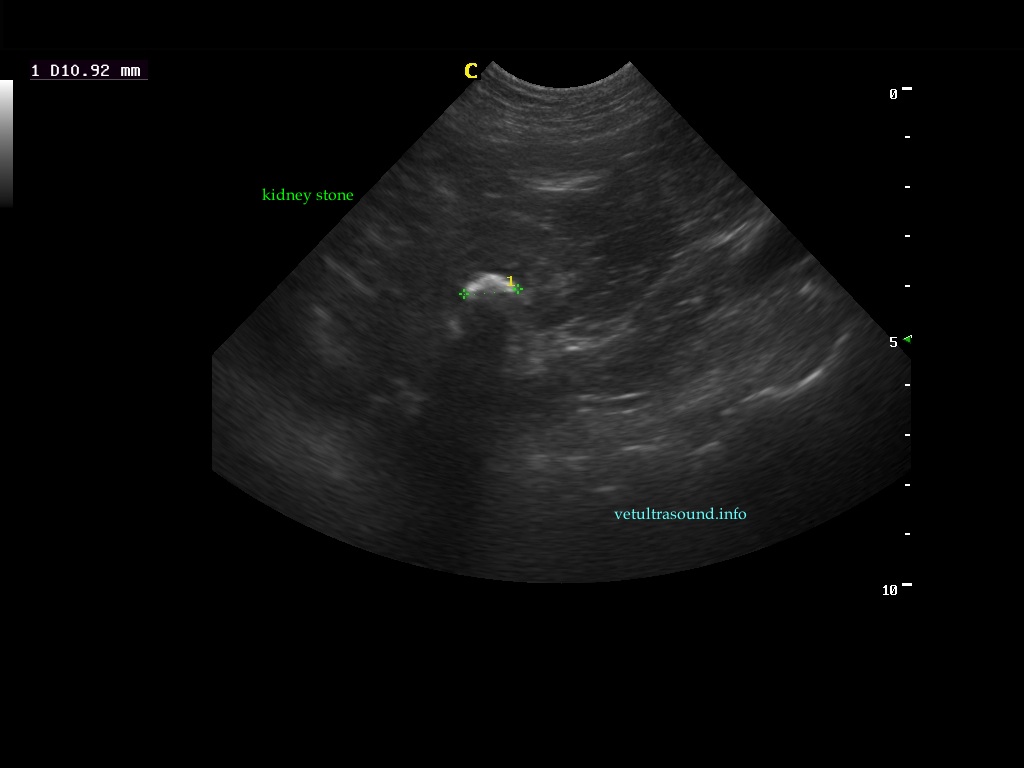

Ευρήματα: Παρουσία λίθου στην πύελο του αριστερού νεφρού ο οποίος καταλάμβανε όλη την κοιλότητά της και εκτεινόταν στο πρώτο τμήμα του ουρητήρα. Ο λίθος προκαλούσε ήπια διάταση του πυελοκαλυκικού συστήματος και του ουρητήρα. Αντίστοιχα στον δεξιό νεφρό βρέθηκε λίθος ο οποίος εντοπιζόταν μόνο στην κοιλότητα της νεφρικής πυέλου. Στην ουροδόχο κύστη βρέθηκε μικρή παρουσία ιζήματος.